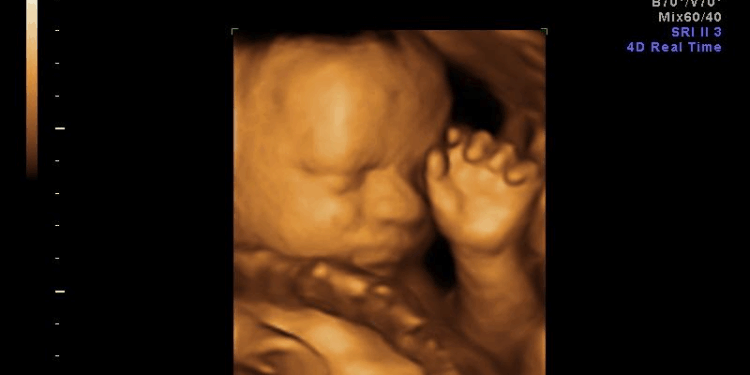

Abortion survivors—those who live through failed procedures—make that dissonance visible. We personify the dissonance. Our very existence strips away any abstraction.

When a child breathes, cries, or moves after an attempted abortion, it’s no longer possible to pretend that what was meant to be destroyed was merely “tissue.” To the abortionist, the survivor becomes the living embodiment of the act’s moral consequence. That fundamental truth is impossible to fully silence, no matter how hard he tries..